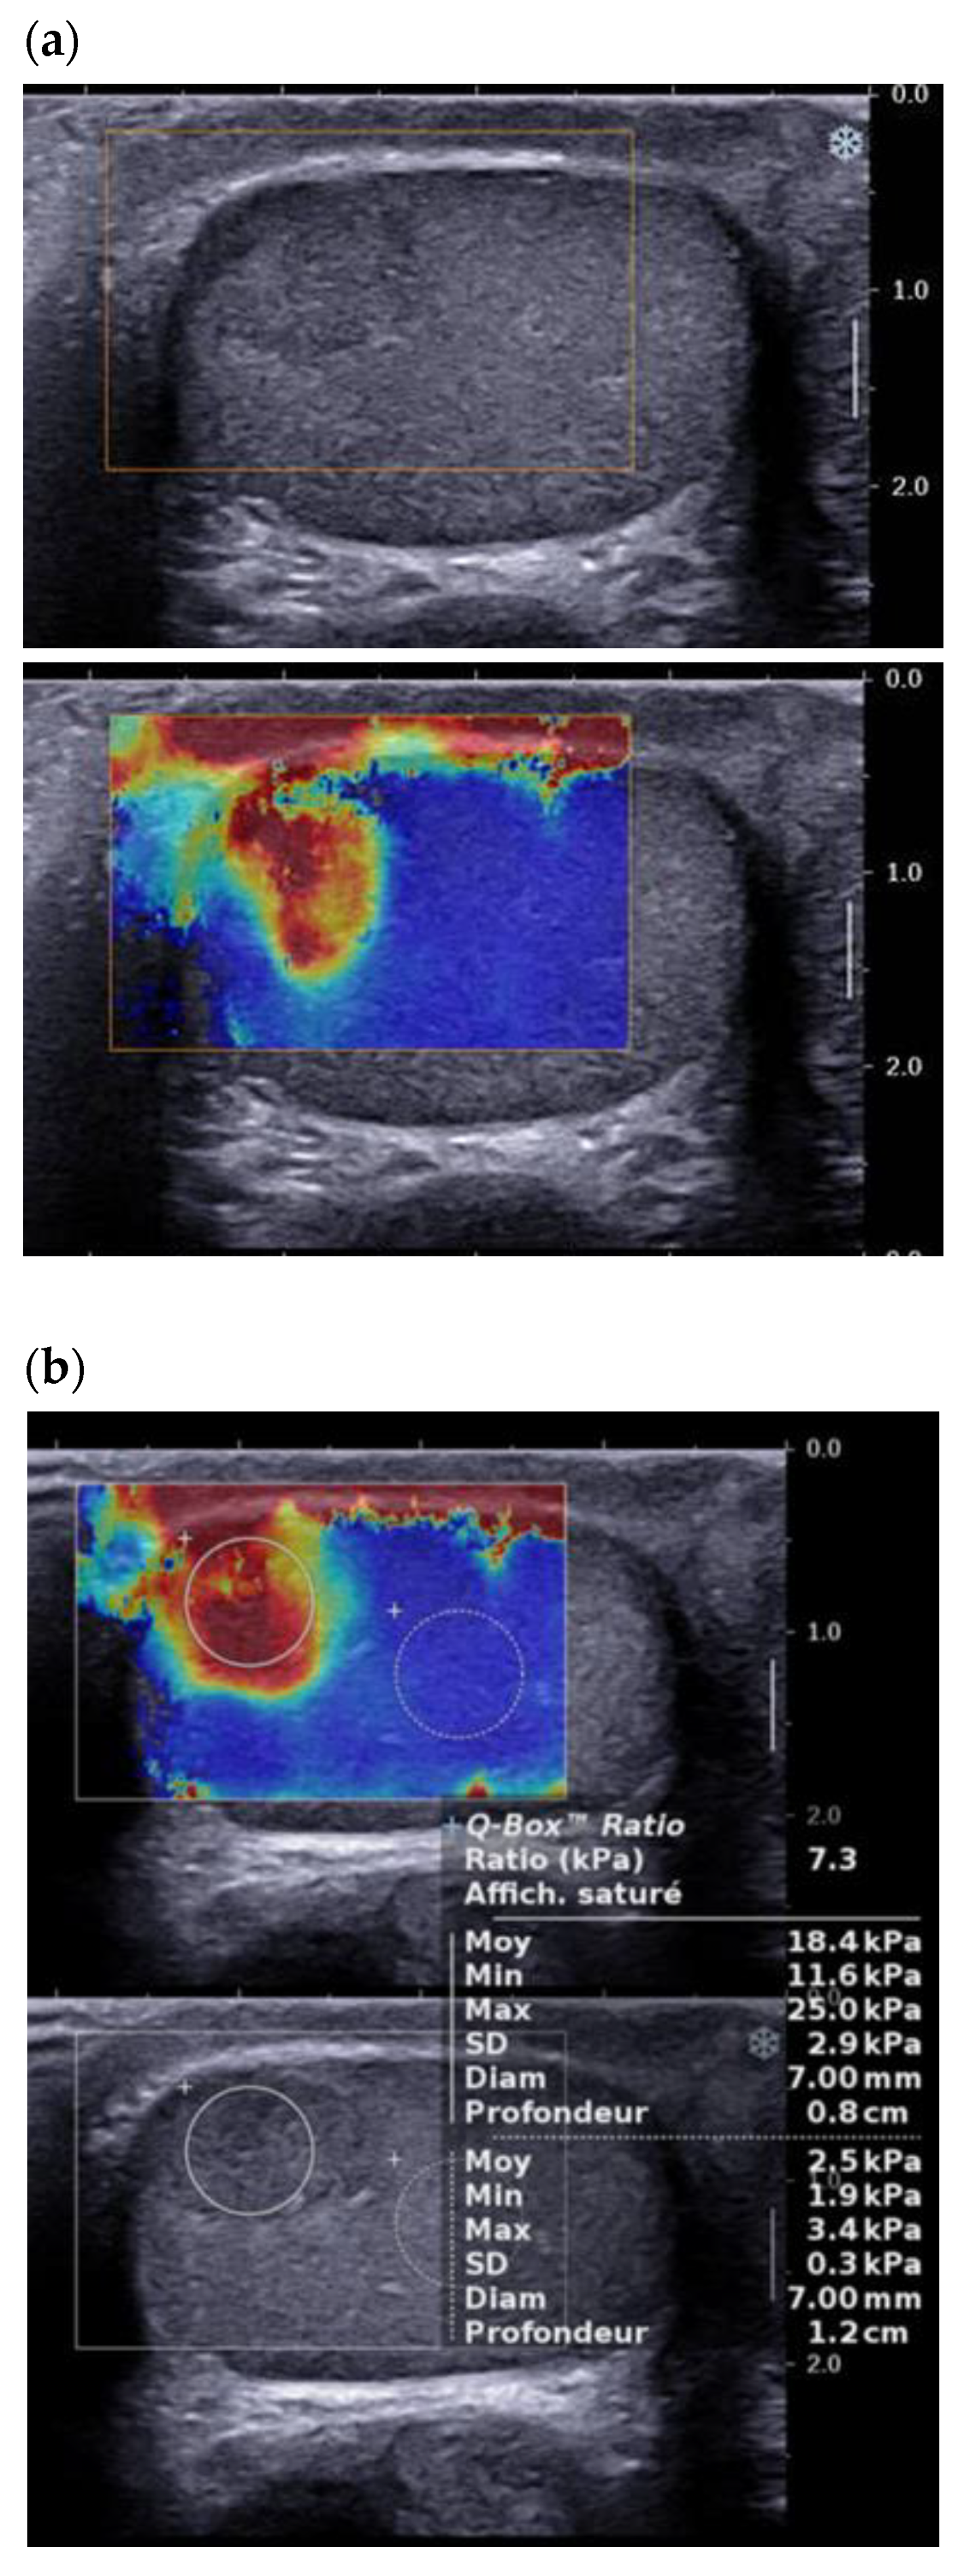

3.4. Elastography